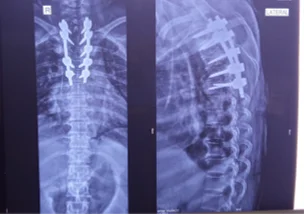

Before & After Clinical Gallery

We showcase real patient cases (with consent), including:

- Pre- and Post-operative MRIs and X-rays

- Disc Herniations, Stenosis, and Spondylolisthesis cases

- Visible improvement in alignment and decompression